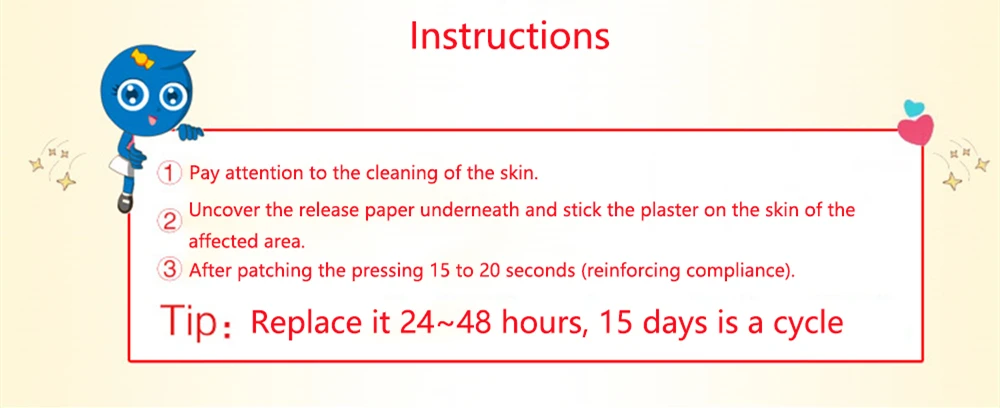

How to Use:

1.Clean and dry affected area

2.Remove the plastic backing from one side of the patch.

3.Smooth that side over the area where you want pain relief.

4.As you remove the other half of the plastic backing, smooth the remainder of the patch over the pain area.

5.Remove from backing film and apply. Remove from the skin after at most 8 -12 hours'application, 4-5 times per week.

1.Clean and dry affected area

2.Remove the plastic backing from one side of the patch.

3.Smooth that side over the area where you want pain relief.

4.As you remove the other half of the plastic backing, smooth the remainder of the patch over the pain area.

5.Remove from backing film and apply. Remove from the skin after at most 8 -12 hours'application, 4-5 times per week.